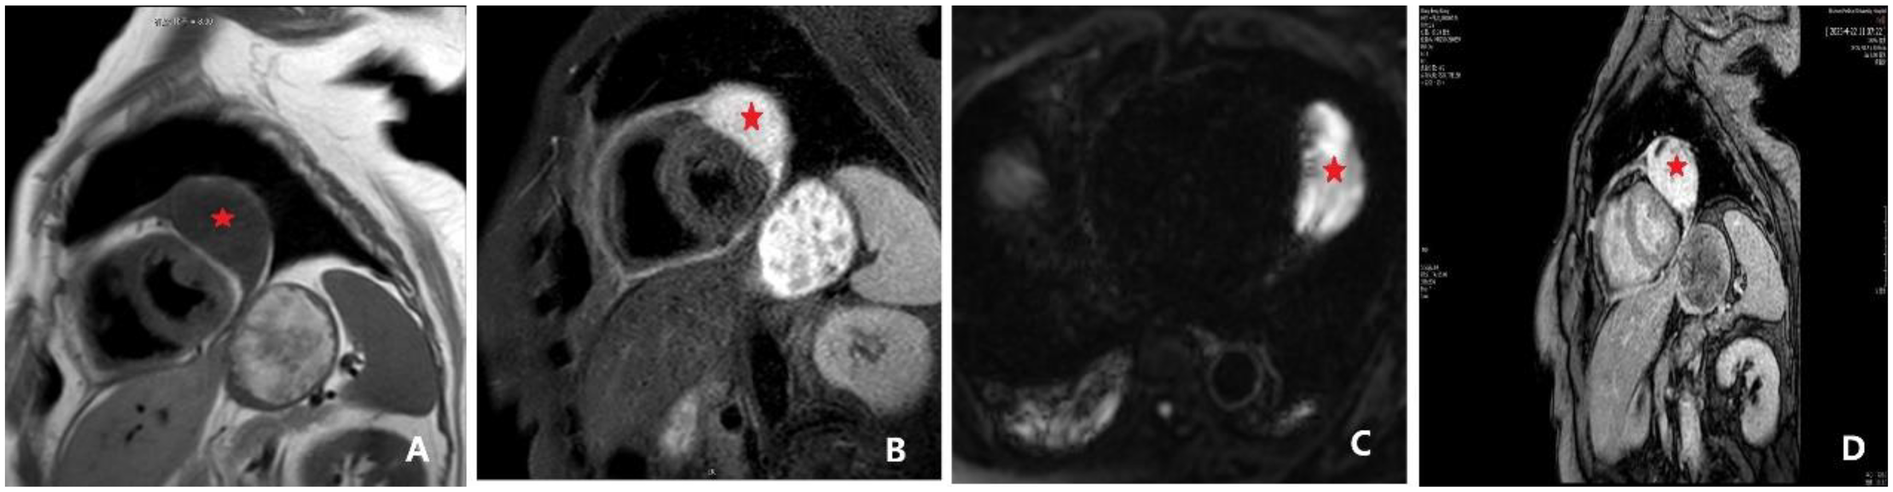

MRI (Figure 3) revealed enlargement of both atria and an oval abnormal lesion (∼37 mm × 62 mm × 61 mm) located laterally within the pericardium; the lesion showed high signal intensity on T2WI, low signal on T1WI, and high signal on DWI and ADC sequences. The lesion exhibited marked heterogeneous enhancement with delayed inward contrast filling, suggesting a possible hemangioma. Early (30–90 s) and late (3–10 min) postcontrast phases demonstrated progressive internal fill-in with delayed enhancement (LGE). Notably, T2-weighted fat-suppression imaging revealed no fat tissue-related signal loss.

Figure 3

Cardiac magnetic resonance (CMR) findings, including late gadolinium enhancement (LGE). (A) Cardiac MRI revealing a space-occupying lesion within the pericardium, lateral to the left ventricle, suggestive of a hemangioma. The findings also included a thickened pericardium with a small amount of effusion. An ovoid lesion with abnormal signal intensity (indicated by *), measuring approximately 37 × 62 × 61 mm, was identified in this location. The lesion appeared hypointense on T1-weighted imaging (T1WI), and a discernible fat plane was present between the lesion and the lateral wall of the left ventricle. (B) Lesion appeared hyperintense on T2-weighted imaging (T2WI). (C) Lesion appeared hyperintense on both diffusion-weighted imaging (DWI) and apparent diffusion coefficient (ADC) maps. Following contrast administration, the lesion demonstrated marked heterogeneous enhancement, with progressive internal fill-in observed on delayed scans. (D) Late gadolinium enhancement (LGE) demonstrating progressive internal fill-in.

Analysis revealed several critical reasons underlying the misdiagnosis. First, inadequate integration of the clinical history played a pivotal role, particularly neglecting the diagnostic significance of previous gluteal liposarcoma of the patient. Recurrent liposarcoma can present notable histological variation, with a predominance of myxoid stroma, which in this case resulted in the initial misdiagnosis as myxoid fibrosarcoma. The fundamental principle of unified diagnosis, recognizing the possibility of recurrence or metastasis from a previous tumor, was overlooked. According to research by Muratori et al. (9), approximately 14% of patients develop metastases, with a notably high rate of extra-pulmonary metastasis (approximately 55%). Frequent metastatic sites include the retroperitoneum, abdominal wall, chest wall, and other fat-rich tissues or organs. Therefore, clinicians should think beyond the conventional view that these tumors primarily occur in the extremities and should include recurrence or metastasis in the differential diagnosis when evaluating tumors at rare locations, especially in patients with a history of soft-tissue sarcomas. Second, significant overlap in imaging features contributed to the misdiagnosis (Table 1). Accordingly, cardiac imaging reports should be framed as a structured differential, explicitly listing benign options (e.g., hemangioma, cyst, hematoma) and malignant possibilities (e.g., myxoid liposarcoma, angiosarcoma, metastasis), stating that delayed enhancement is shared across both categories. In this case, MRI findings closely resembled a hemangioma, with both lesions showing high T2WI signals and delayed enhancement. However, heterogeneous enhancement and delayed contrast filling could easily be misinterpreted as benign characteristics (10).